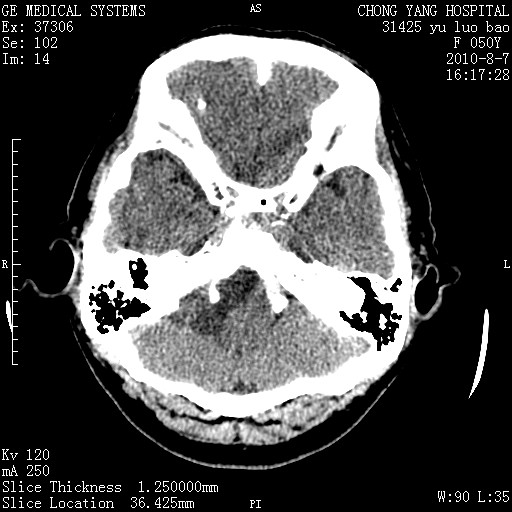

右侧桥小脑角区占位--听神经瘤,建议增强或mri检查。

右侧桥小脑角去等密度占位,右侧内听道扩大、骨质吸收,考虑:右侧听神经瘤,建议增强检查。

右侧内听道扩大、骨质吸收,中脑受压左移,考虑:右侧听神经瘤,建议增强检查。支持!

右侧桥小脑角区等密度占位,内耳道扩大,听神经瘤